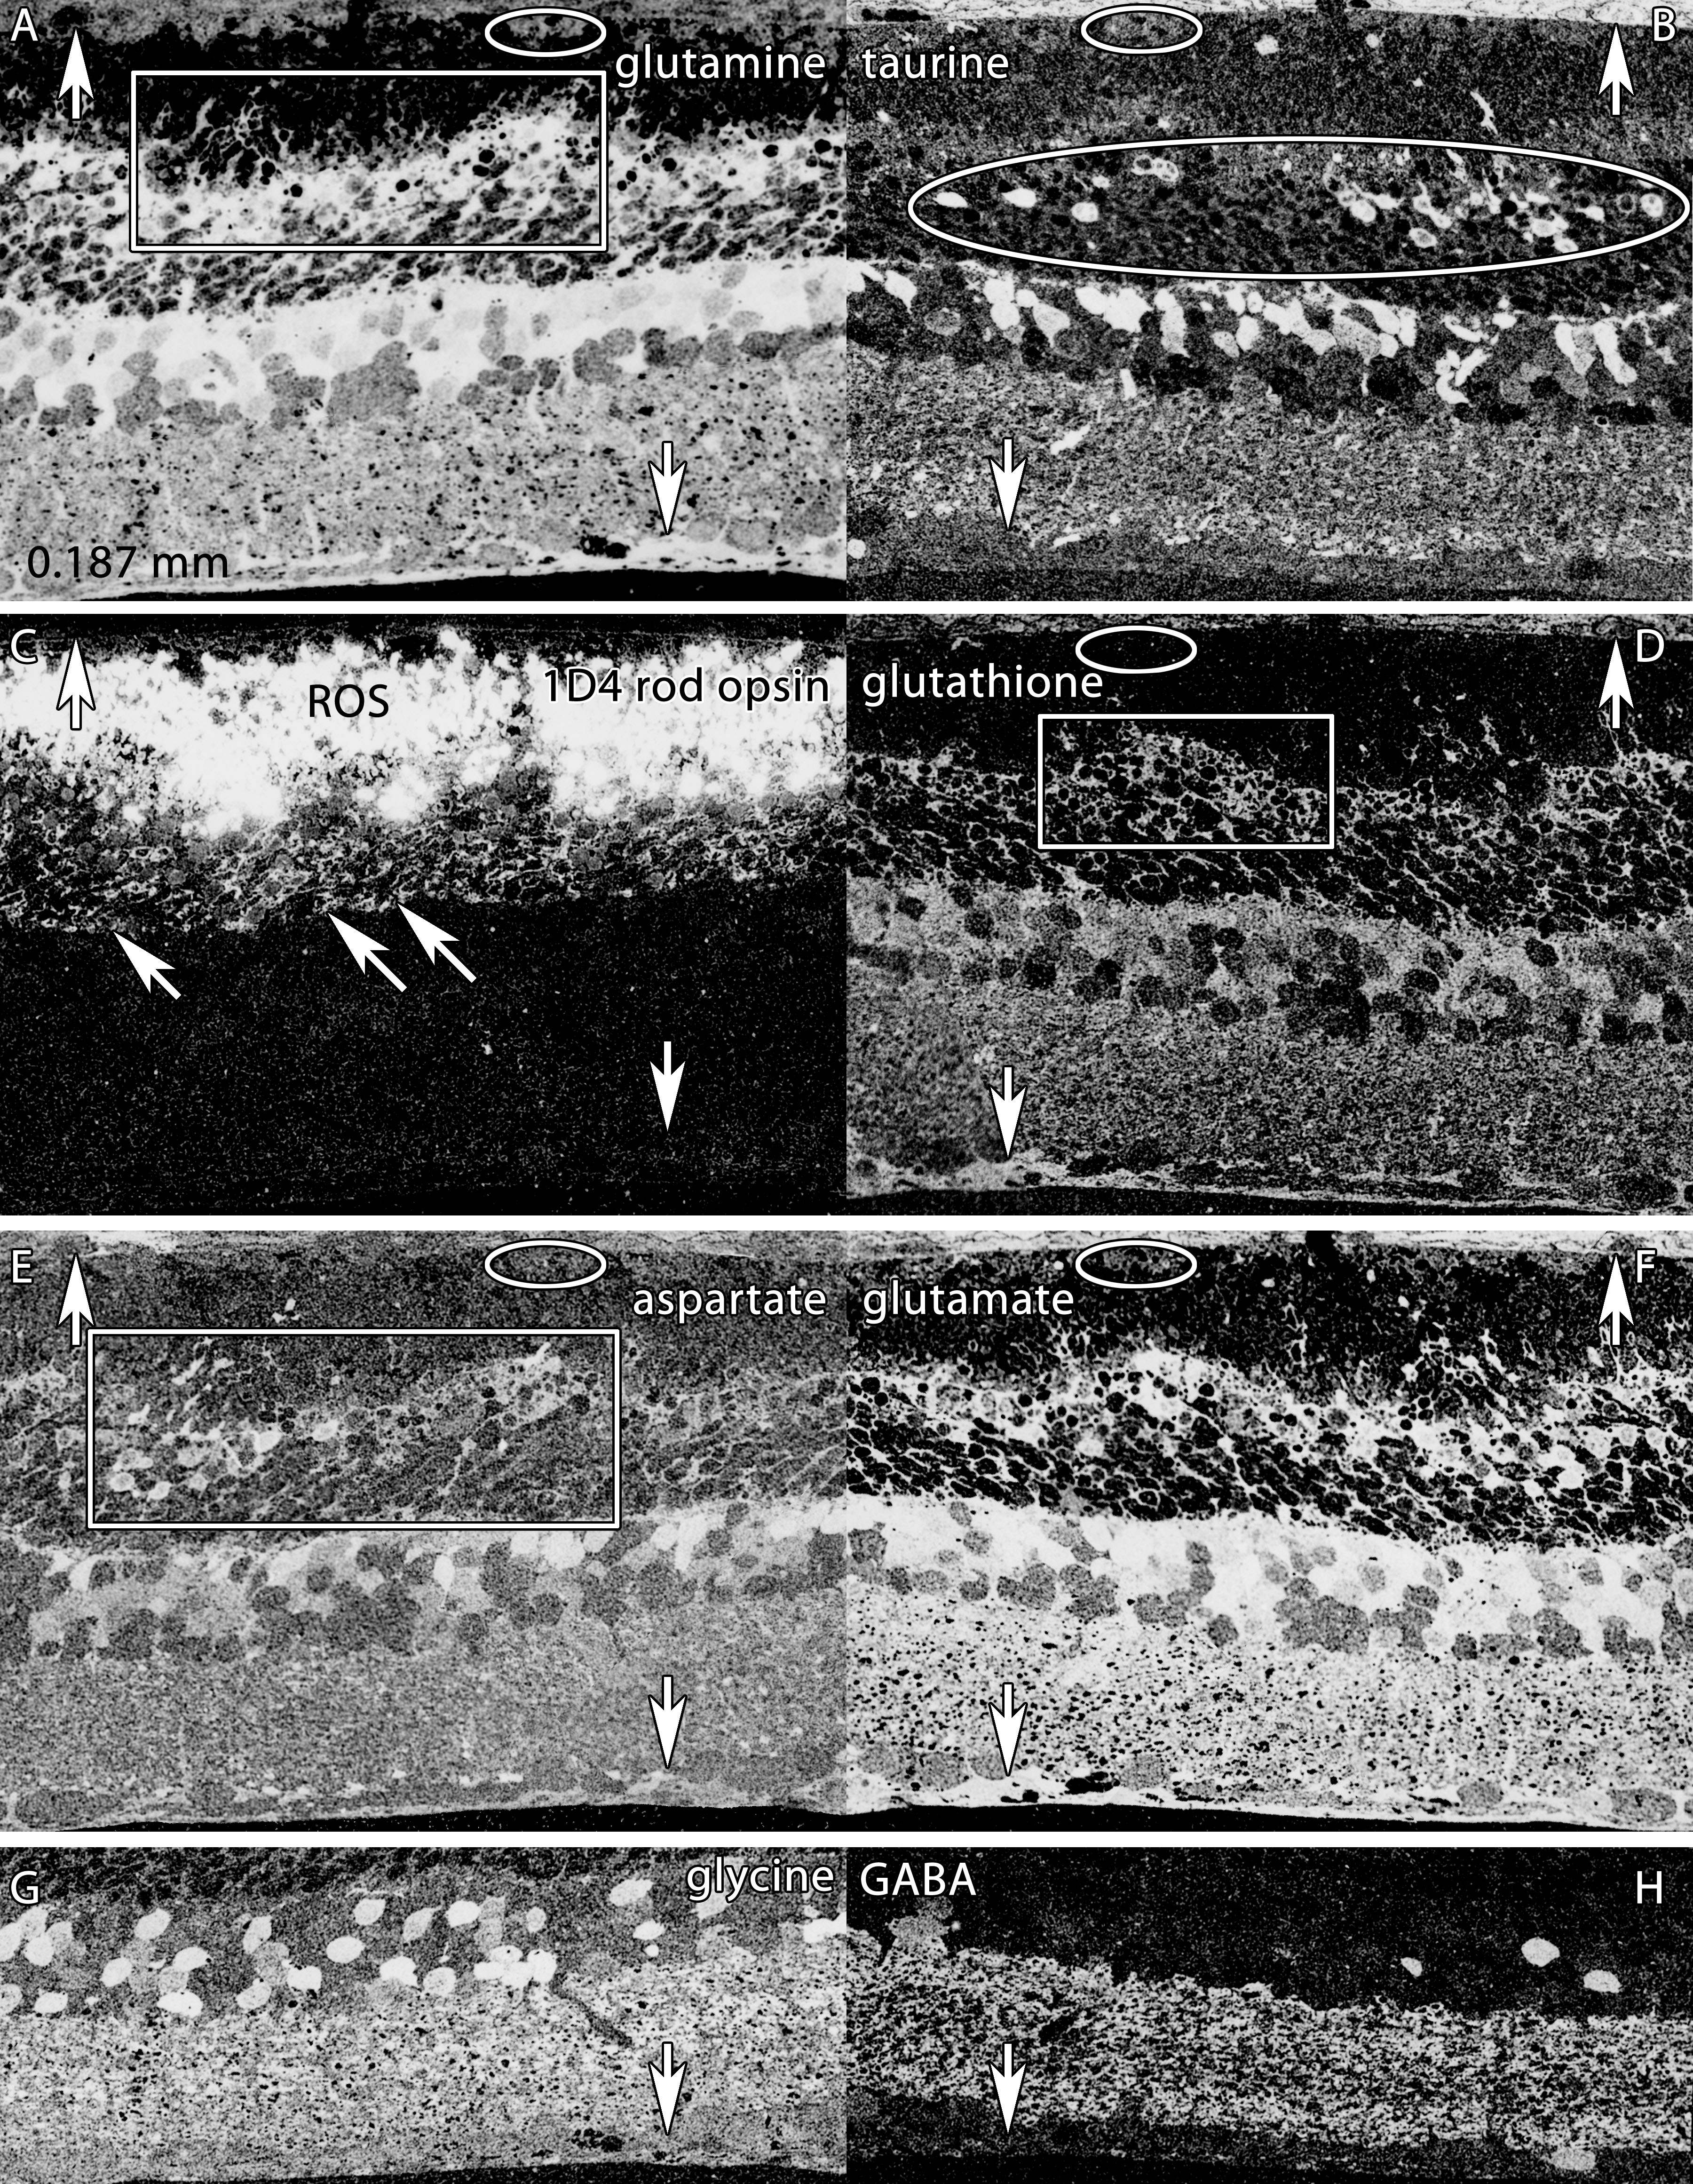

Figure 4. Altered molecular signatures immediately after 48 h of light exposure. Visualization: Quantitative gray-scale images displayed

as intensity in mirror-image pairs (AB, CD, EF, GH). Up arrows, choroid-retinal pigment epithelium (RPE) interface; down arrows, Müller cell (MC) end feet; oblique arrows mark

the border of the outer nuclear and outer plexiform layers. Scale: All panels are 0.187 mm wide. A: Glutamine signatures are elevated in MCs, with hypertrophy of distal MC processes at the external limiting membrane (box).

The RPE layer is severely damaged, with only a few distinct cells (oval). B: Massive taurine depletion in MCs (down arrows) and abnormal elevation in photoreceptors (oval) and bipolar cells. C: 1D4 rod opsin reveals extreme disorganization of rod outer segments and extensive mislocalization of rod opsin into rod somas.

D: Glutathione signatures highlight the disorganization of MC processes in the outer retina. E: Aspartate signals are abnormally high in rod inner segments. F: Glutamate signals in particular are abnormally elevated in MCs. G, H: Glycine and γ-aminobutyric acid (GABA) signals seem essentially normal, with no evidence of ischemia or excitotoxicity. Sample

metadata: SD Rat, age at LX 60 d, animal #P60–1L-48, left eye, 48 h LX, harvested at 0 days pLX, bloc code 6464, slide code